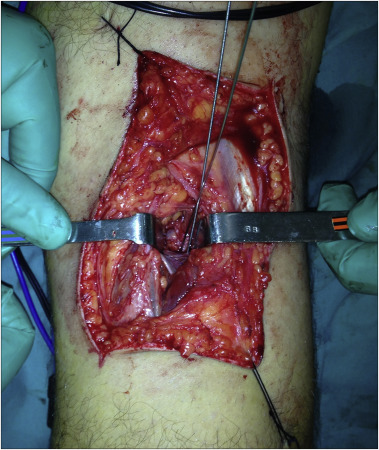

Under spinal anesthesia and tourniquet control, physical examination followed by standard diagnostic knee arthroscopy was performed at the second day. During arthroscopy, the ACL was found edematous but it was intact and pivot shift test was negative. There was grade I medial laxity indicating MCL injury. Both menisci were found intact with arthroscopic examination. There was no cartilage lesion in femoral condyles. The avulsion fracture of the PCL was extending to the lateral tibial plateau, PCL was found to be lax with probing. After the diagnostic arthroscopy, the patient was turned to prone position, and S shaped incision was made over the popliteal fossa. A meticulous dissection was made down to the posterior capsule with sparing medial and lateral head of gastrocnemius muscle. The capsule was cut longitudinally and the fracture fragment was exposed. Under fluoroscopic control, the fragment was temporarily fixed with two Kirschner wires and two headless cannulated compression screws were used to fix the fracture (Fig. 3 ). The postoperative period was uneventful. Patient wore a knee brace and active knee range of motion exercises was started and gradually increased without weight bearing during the first 6 weeks. At the 6th week weight bearing was allowed. At the final follow-up 18 months after the initial injury, the patient was free of pain and returned to her previous level of activity and work. Final knee radiographs showed the union of PCL avulsion fracture (Fig. 4 ). Knee range of motion was normal (between 0 and 130°) and painless. Anterior drawer test, Lachman test, posterior drawer test and medial and lateral stress tests were all negative. There was no ligamentous laxity or instability. Meniscus examination test including joint line tenderness, McMurray and Apley tests were negative both for medial and lateral menisci. Lysholm Knee Score was 100 points and rated as excellent.

Fig. 3

Fig. 3.

Intraoperative appearance of the patient with popliteal posterior approach just after the provisional fixation with two Kirschner wires.